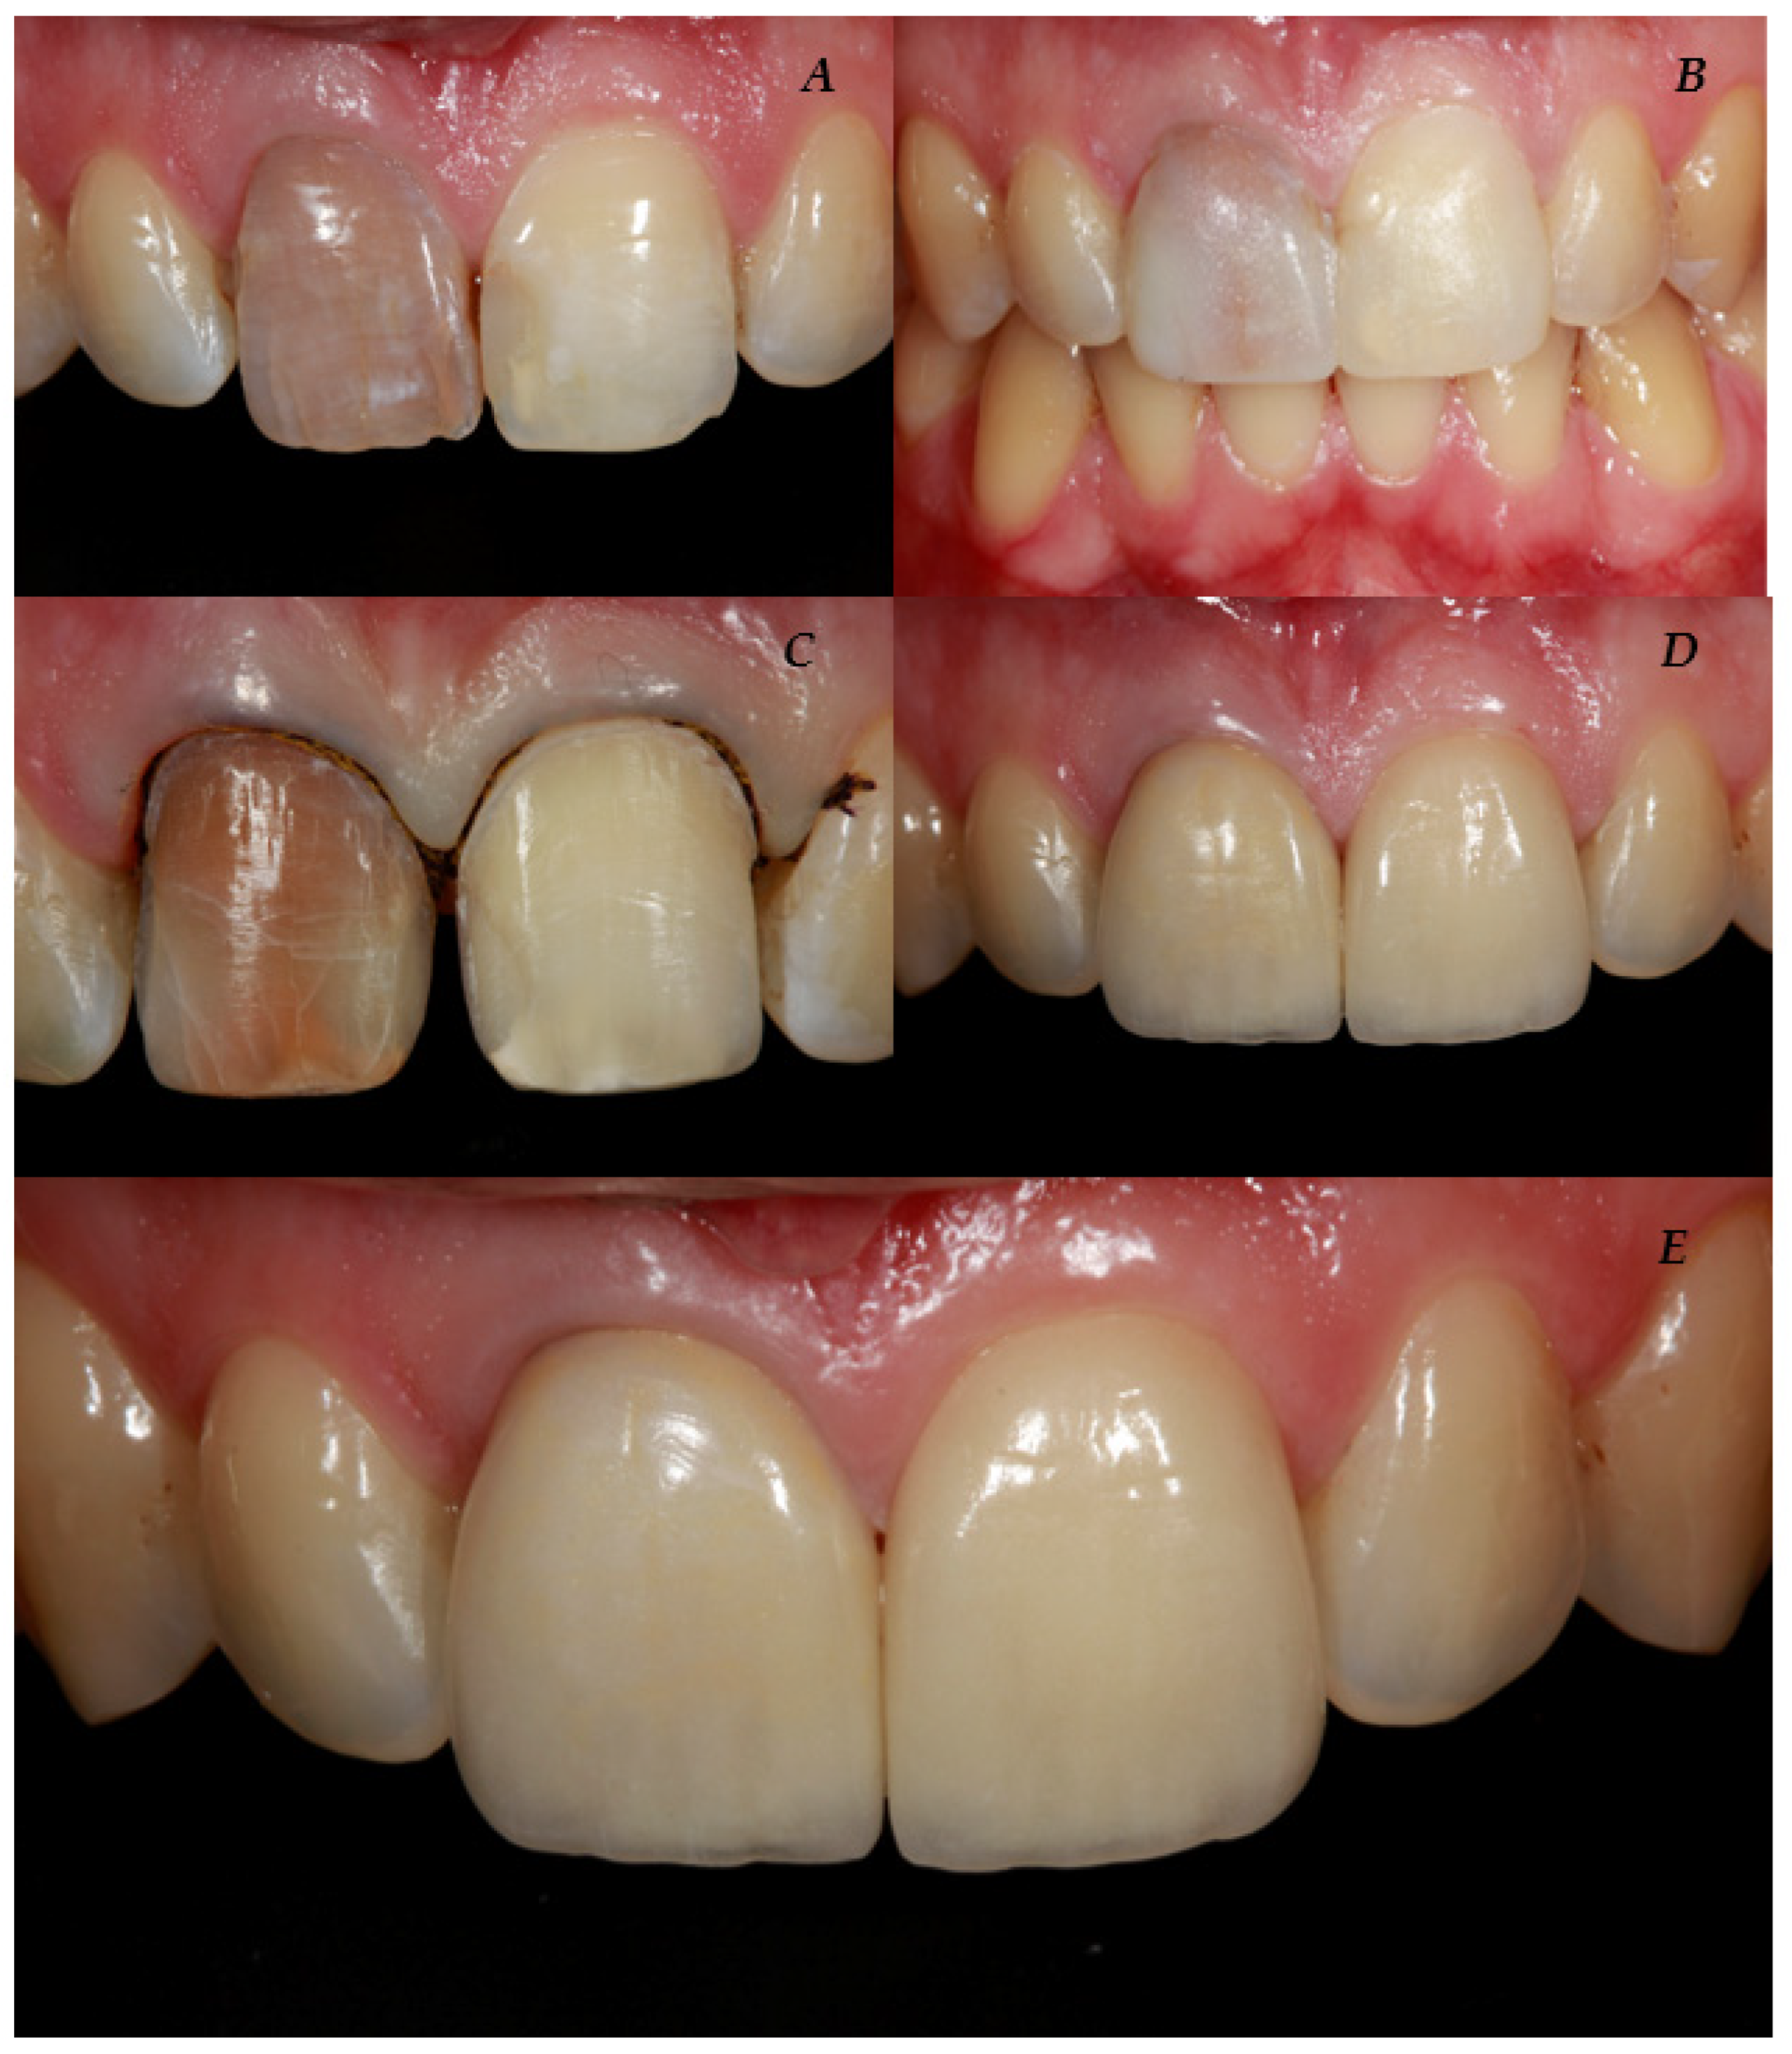

2.2. Pre-Treatment Procedures

2.3. Tooth Preparation Procedure

2.5. Temporalization

2.7. Clinical Try-In and Luting Procedure